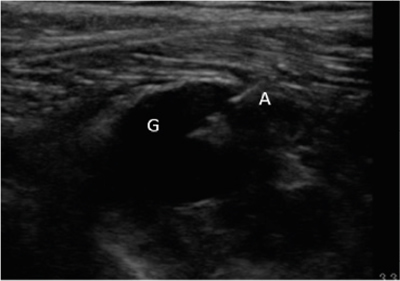

Neuropatía peronea secundaria a ganglión extraneural: revisión de literatura y propuesta de tratamiento. Caso no positivo

Este artículo presenta el caso de un paciente de 69 años con una neuropatía compresiva peronea secundaria a un ganglión, inicialmente interpretada como una radiculopatía L5. Este incorrecto enfoque supuso la sobremedicación del paciente, un mal control algésico, la realización de una discectomía L4-L5 innecesaria y una pobre evolución neurológica.

Un enfoque diagnóstico correcto y un abordaje terapéutico precoz habrían supuesto una mayor mejoría clínica e incluso una recuperación neurológica completa del paciente. Por ello, este caso sirve para resaltar: a) el valor de la ecografía en neuropatías periféricas como herramienta diagnóstica y pronóstica y el de la ecografía en gangliones como arma diagnóstico-terapéutica; b) el uso de las pruebas diagnósticas como apoyo a una exploración física exhaustiva, y no como diagnóstico en sí mismas, y c) la importancia de la publicación de casos no positivos para optimizar recursos, evitar repetir errores, reducir el sesgo de publicación y facilitar el inicio de proyectos de investigación.

Figura 1

Figura 2